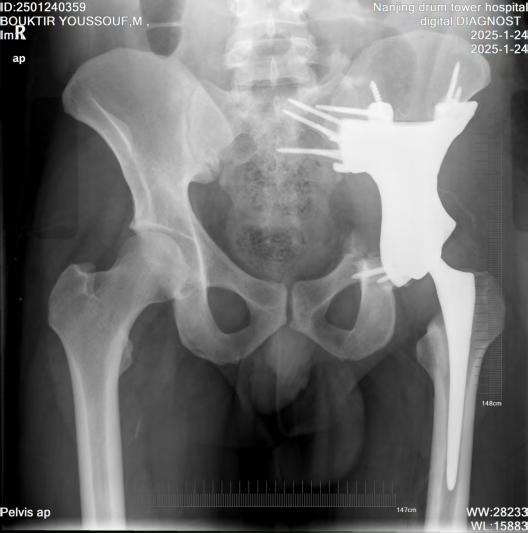

2025年1月4日,BOUKTIR YOUSSOUF入院,王守丰主任医师团队与其及家属进行了全面沟通,详细解释了手术方案和预期效果。1月13日,团队成功为BOUKTIR YOUSSOUF实施了“骨盆病损切除术+骨盆重建术”。手术过程很顺利,术后患者疼痛逐渐缓解,切口愈合良好。

手术前后对比